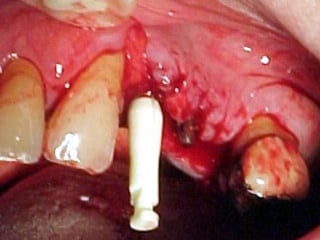

Lingitud de hueso

Disponible 20 mm.

Implante en posición

Dejamos el implante sepultado por 4 meses previos al inicio del procedimiento

Protésico.